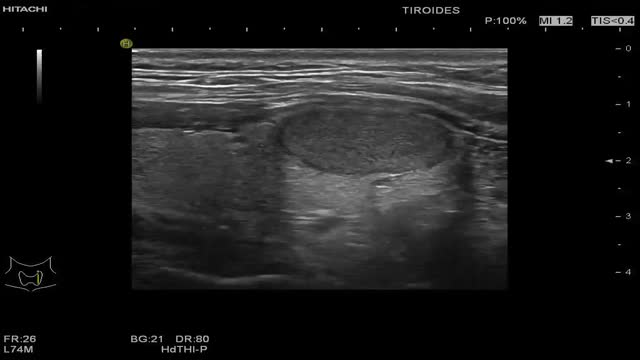

0 puntos: TIRADS 1 (probabilidad de malignizar <2%). Clasifica el nódulo como benigno. No requiere PAAF (fig. 2 y video 1)

- –

2 puntos: TIRADS 2 (probabilidad de malignizar <2%). Clasifica el nódulo como no sospechoso. No requiere PAAF (fig. 3 y video 2)